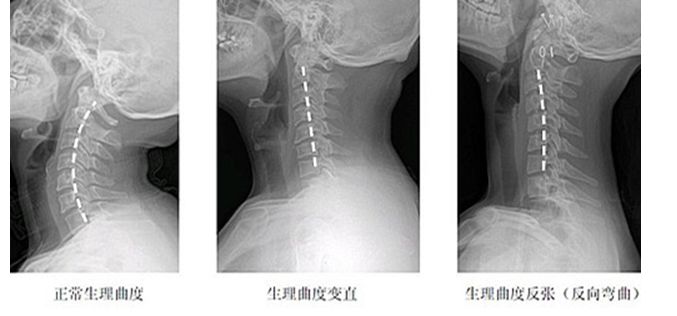

颈椎疾病普遍遇到一个问题,就是颈椎曲度变直,颈椎没有生理曲度,甚至反弓,影像报告上会清楚的注明:颈椎曲度浅直、变直或消失。但是很多医生是回避颈椎曲度变直这个问题,患者也自然忽视颈椎曲度消失这个情况,只知道颈椎间盘突出,严重了需要手术,却不了解颈椎曲度变直或消失与颈椎间盘突出的必要联系。

在临床上发现,很多核磁影像与X光影像对比,几乎所有颈椎间盘突出与颈椎变直是同时存在,就不得不考虑颈椎曲度变直与颈椎间盘退化的必要联系。

颈椎在应该形成正常生理曲度的时候没有形成,就变成了今天我们拍摄X光显示的颈椎曲度变直,反弓。